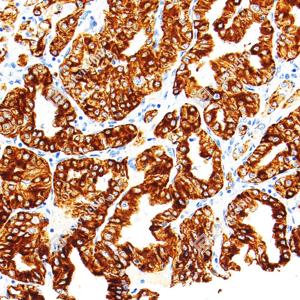

IHC检测Cytokeratin 18蛋白(货号 GB15232). 样品: 人胃, 4%多聚甲醛 (货号G1101) 固定12-24小时. 抗原修复: 柠檬酸抗原修复液(干粉, pH 6.0) (G1201), 高压锅均匀喷气计时2分钟. —抗: 1: 500稀释, 4℃ 孵育过夜. 二抗: S-vision免疫组化多聚二抗(山羊抗小鼠), 即用型(货号G1301), 室温孵育20分钟. |